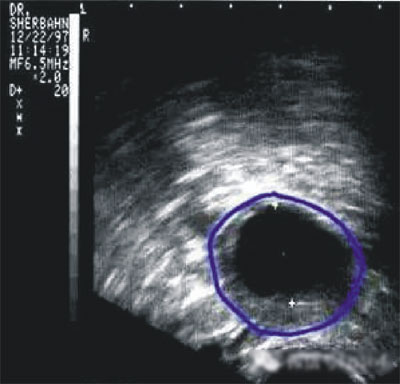

第三步:排卵監(jiān)測

常用的監(jiān)測排卵方法有基礎(chǔ)體溫測定(BBT)、陰道B超監(jiān)測排卵、血清性激素測定等。

陰道B型超聲動態(tài)監(jiān)測卵泡的發(fā)育及排卵,是監(jiān)測排卵最準(zhǔn)確可靠的方法。通過陰道B超檢查可以了解子宮及雙側(cè)附件(卵巢和輸卵管)區(qū)的基本情況,測定卵巢內(nèi)的竇卵泡計數(shù),評估卵巢儲備功能,動態(tài)監(jiān)測排卵。